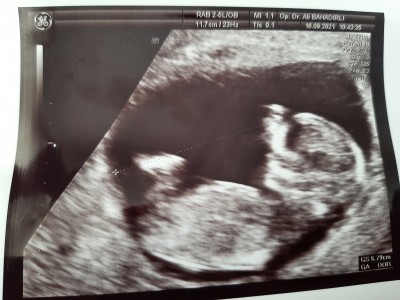

17 Eylül 2021 Hamilelik Dönemi Genel kategorisinde (10 puan) sordu

Kızlar merhaba aranızda cinsiyet tahmini yapabilen var mı tahminlerinizi bekliyorum

Gebelik haftası 12+5

Erkeğe benziyor ama daha erken net bisey söyleyemem dedi